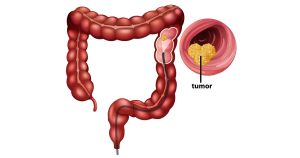

Você pode reduzir o risco de câncer no intestino, e tudo começa pelos seus hábitos de hoje

O câncer colorretal é o segundo tipo de...

Leia mais#MARÇOAZUL: sinais de alerta do câncer colorretal que não devemos ignorar

O mês de conscientização sobre o câncer colorretal...

#MARÇOAZUL: sinais de alerta do câncer colorretal que não devemos ignorar

O mês de conscientização sobre o câncer colorretal reforça um alerta importante: esse é um dos tipos de câncer mais comuns e também um dos